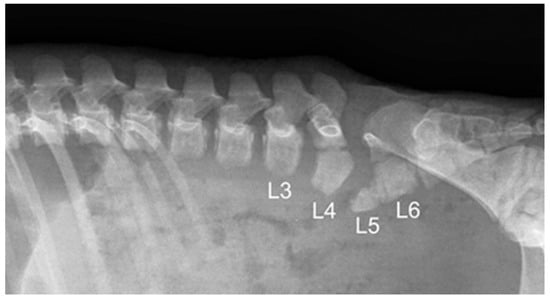

| 1 * | None | partial aplasia of L4, quite complete aplasia of the vertebral canal of L5, partial aplasia with absence of the vertebral canal of L6; scoliotic deviation toward the right. | partial aplasia of S1 with absence of the vertebral canal. | Coccygeal vertebrae: no visible abnormalities other abnormalities: duplication of the first tract of the ureters; caudal dislocation of the left kidney with a dorso-medial bended shape and some cortical small cists |

| 2 * | None | the lumbar tract showed a lordotic and scoliotic curvature; L2-L3-L4 were irregularly fused and L3-L4 without a vertebral canal; L5 and L6 were present only as a bud of the body with the agenesia of the vertebral arch. | S1 and S2 missed the vertebral canal and were irregularly articulated | Coccygeal vertebrae: only the first five metameric were visible |

| 3 * | None | the lumbo-sacral junction showed a slight lordotic curvature; L6 missed the vertebral canal. | S1 was present only as a bud of the body with the agenesia of the vertebral arch | Coccygeal vertebrae: Only four coccygeal vertebrae were present. |

| 4 ** | T14 was partially fused with L1. | L1 was partially fused with T14 and its body was wedge shaped (hemi vertebra) L2 had a dysplastic vertebral canal and was partially fused with L3; the residual lumbar vertebrae were present only as a bud, without a vertebral canal and with a scoliotic curvature toward the left | S1 was present as a small bud, the remnant were partially fused and with a kyphotic curvature. | Coccygeal vertebrae: Visible until the Co15 with some hemi vertebrae. Other abnormalities: Partial fusion of the left 13th and 14th ribs; the pelvis was tilted toward the left; severe hyper extension of the left knee with inversion of the normal angle. |

| 5 ** | Visible T16 with a complete aplasia of the vertebral canal. | vertebrae L1 had only a slight mineralization of the body and the remnant (L2-L6) were present only as a bud of the body with a complex lordotic-scoliotic curvature toward the right. | the body of S1 was partially fragmented and without the vertebral canal; S2 was visible only as a small bud; no other sacral vertebrae were visible. | Coccygeal vertebrae: The coccygeal vertebrae were absent. Other abnormalities: both the knees had an inverted angle. |

| 6 ** | Visible T15 | partial aplasia of L2 with an incomplete vertebral canal; L3 without the vertebral canal and a right fragmented lateral process; the remnant lumbar vertebrae (L4-L6) were present only as a bud of the bodies and with a lordotic curvature. | partial dysplasia of the body of S1 with a not fused cranio-ventral portion of the body and without the vertebral canal. | Coccygeal vertebrae no visible abnormalities. |

| 7 ** | None | partial aplasia of L4 without the vertebral canal; L5 and L6 were present only as a small bud of the bodies. | no visible abnormalities | Coccygeal vertebrae no visible abnormalities Other abnormalities Severe hyper extension of both the knees and the tarsi. |

| 8 ** | None | L1 was dysplastic with bifid dorsal process and the vertebral canal communicating with the dorsal soft tissues of the lumbar tract; absence of the vertebrae from L2 to L4; L5 and L6 partially fused and with aplasia of the vertebral canal. | Sacral vertebrae S1 and S2 were partially fused and irregularly fragmented without the vertebral canal. | Coccygeal vertebrae no visible abnormalities. |